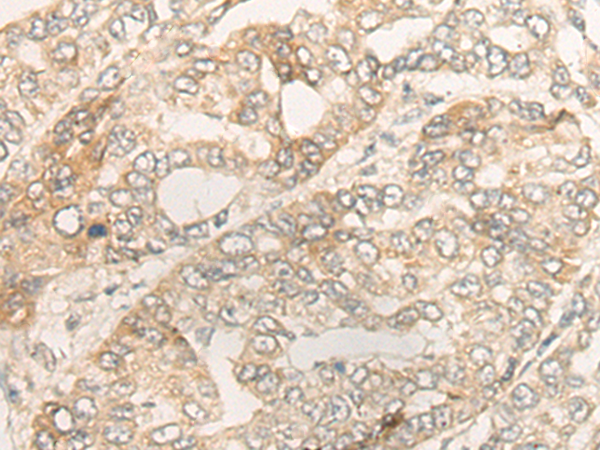

The image is immunohistochemistry of paraffin-embedded Human liver cancer tissue using 47081(DUOX2 Antibody) at dilution 1/40. (Original magnification: ?00)